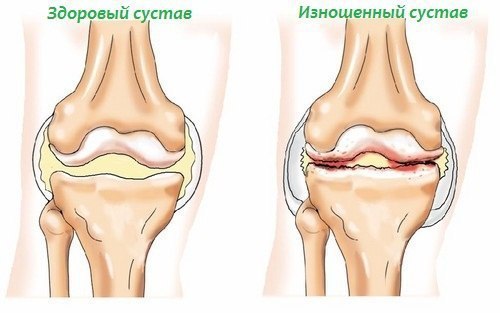

Систематическая травматизация хряща ведет к развитию остеоартроза - заболевание, которое сопровождается выраженными болевыми ощущениями в суставах, нарушением двигательной активности и носит практически необратимый характер, то есть зачастую приводит к инвалидности. Около 20 миллионов американцев страдает этим заболеванием, и как показывают статистические данные, риск возникновения этой патологии значительно выше при занятиях силовыми видами спорта.